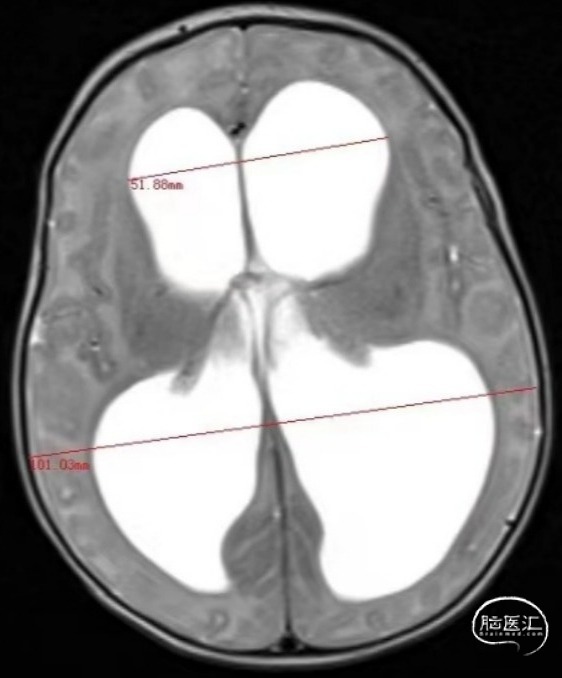

术前头颅CT

Evans index(EI)≈0.5